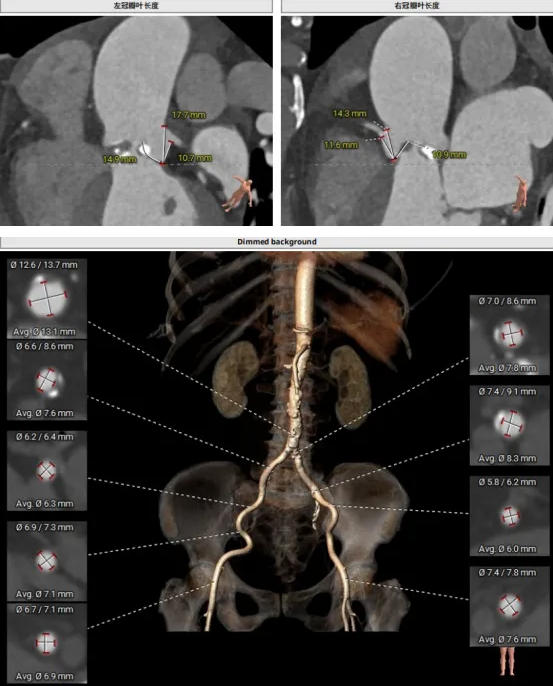

CT結(jié)構(gòu)評(píng)估

患者為功能性二葉瓣,瓣葉增厚,輕度鈣化,鈣化主要集中在左竇瓣葉上,左冠脈高度較低,結(jié)合瓣葉長度,竇部結(jié)構(gòu)綜合評(píng)估左冠風(fēng)險(xiǎn)較低,但左冠瓣葉瓣尖處有鈣化團(tuán)塊,在球擴(kuò)以及瓣膜釋放時(shí)仍需注意左冠灌注情況,由于鈣化團(tuán)塊位置特殊,建議做冠脈保護(hù)處理,右側(cè)股動(dòng)脈作為主入路,穿刺點(diǎn)位于股骨頭中段即可。